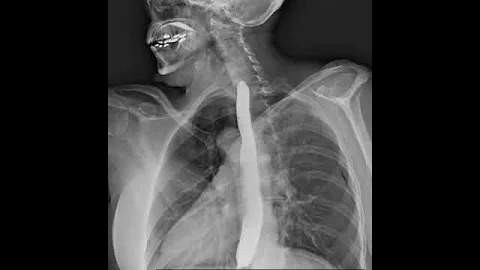

How X-rays See Through Your Skin - Ge Wang